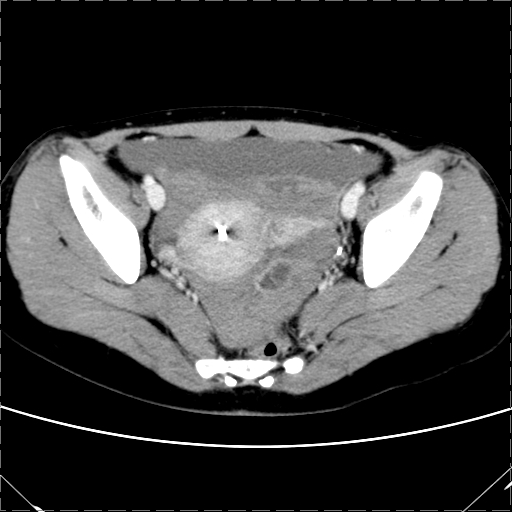

女 29岁 突然腹部疼痛1天 b超示子宫左后方肿块。月经正常。

影像表现复杂,膀胱上见一囊性包块,比膀胱密度高,其内有不均匀稍高密度,似与道格拉斯窝肿物无分界,病灶没有张力,因其腹平坦,推定其具有流动性,但又似见包膜,而b超没有报告这一现象。确实没见过。考虑卵巢囊肿蒂扭转并囊内出血可能。

病变主要位于道格拉斯窝,而且大体形态比较扁平且贴合子宫直肠,无明显张力及对周围脏器压迫,所以考虑为液体,而中间可见囊样病变伴环形强化,期内还可见分隔影,结合突发急性腹痛故多考虑囊腺瘤伴破裂出血。

腹腔镜术后 卵巢黄体囊肿破裂出血